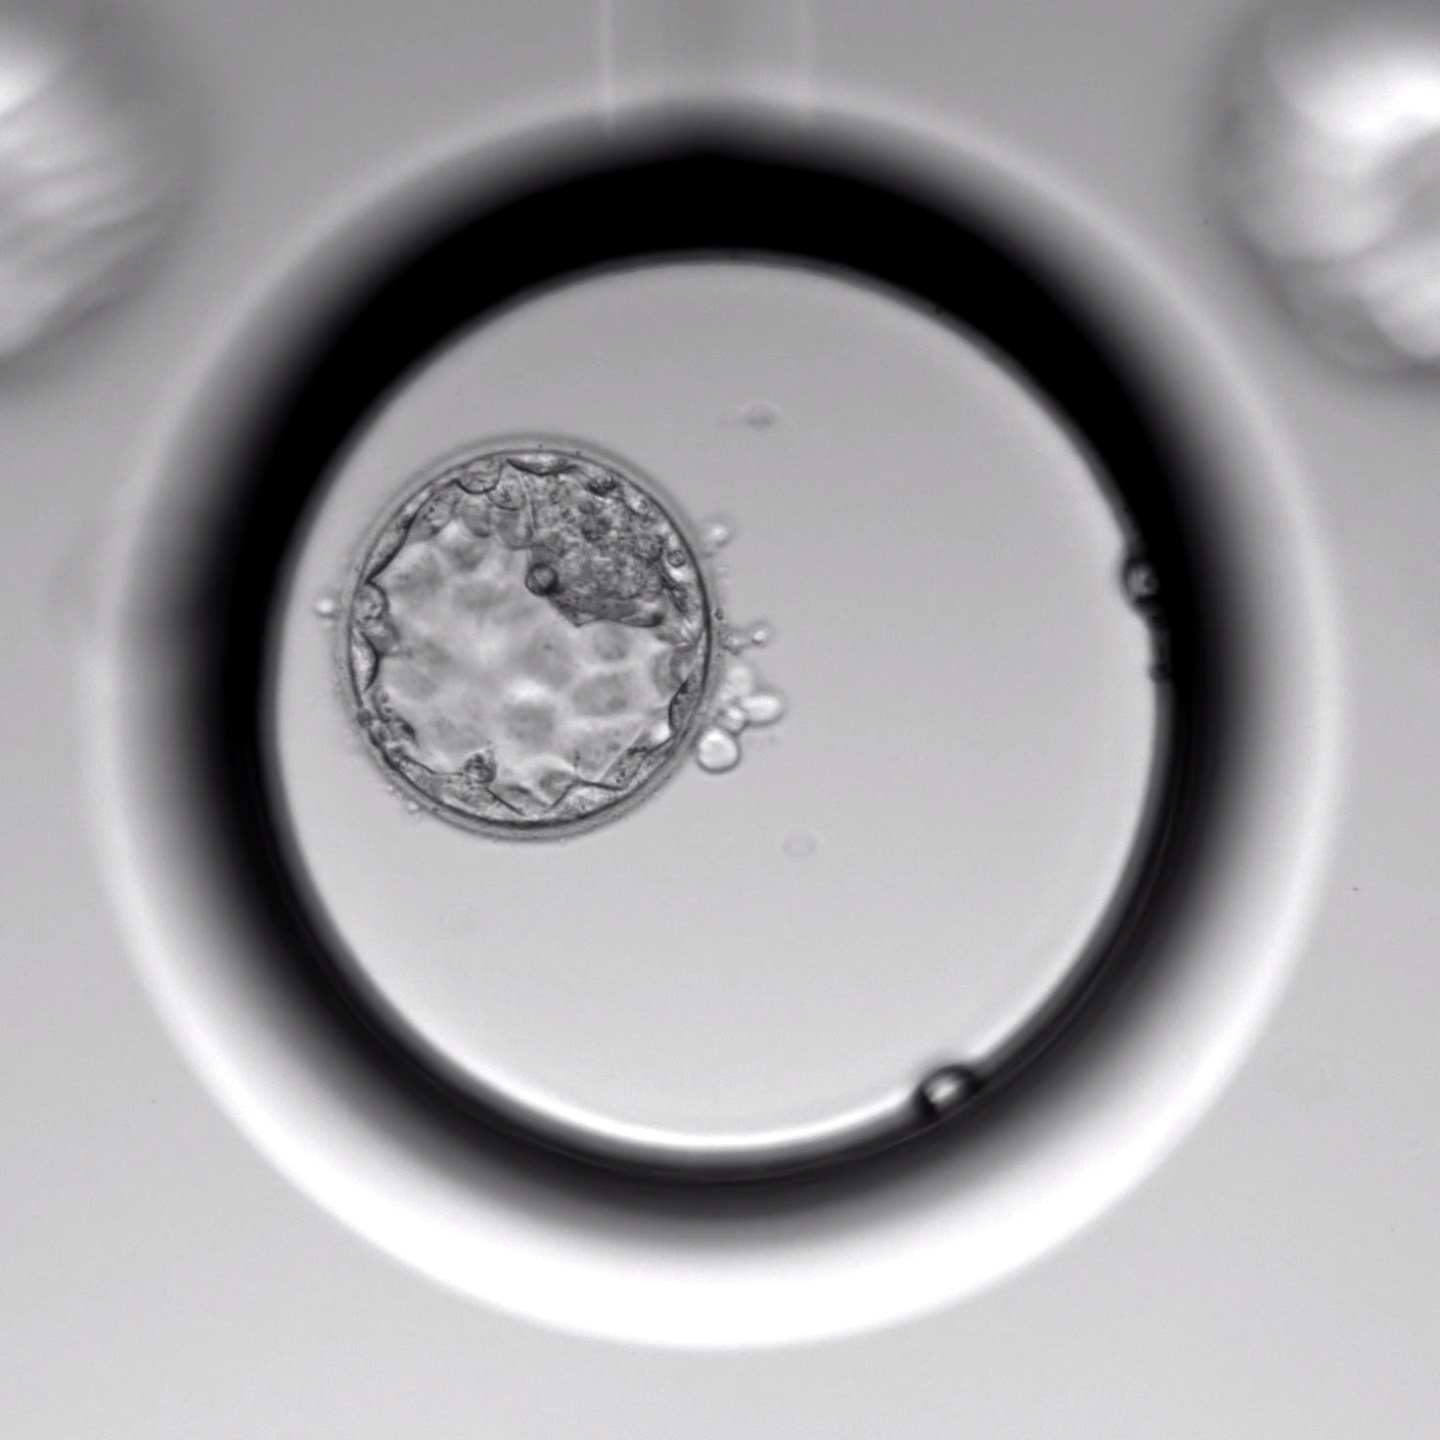

La Fecundación in vitro (FIV) es un procedimiento en el que la fecundación del óvulo tiene lugar en el laboratorio. Posteriormente, los embriones permanecen en un incubador entre 3 y 5 días, hasta transferirlos dentro del útero materno o vitrificarlos (congelarlos).

A partir de ese día comienza el trabajo en el laboratorio con la fecundación de los óvulos. Cuando los embriones llegan a la fase de blastocisto (día +5 de desarrollo embrionario), pueden ser transferidos, vitrificados o biopsiados para estudio genético, según el caso.